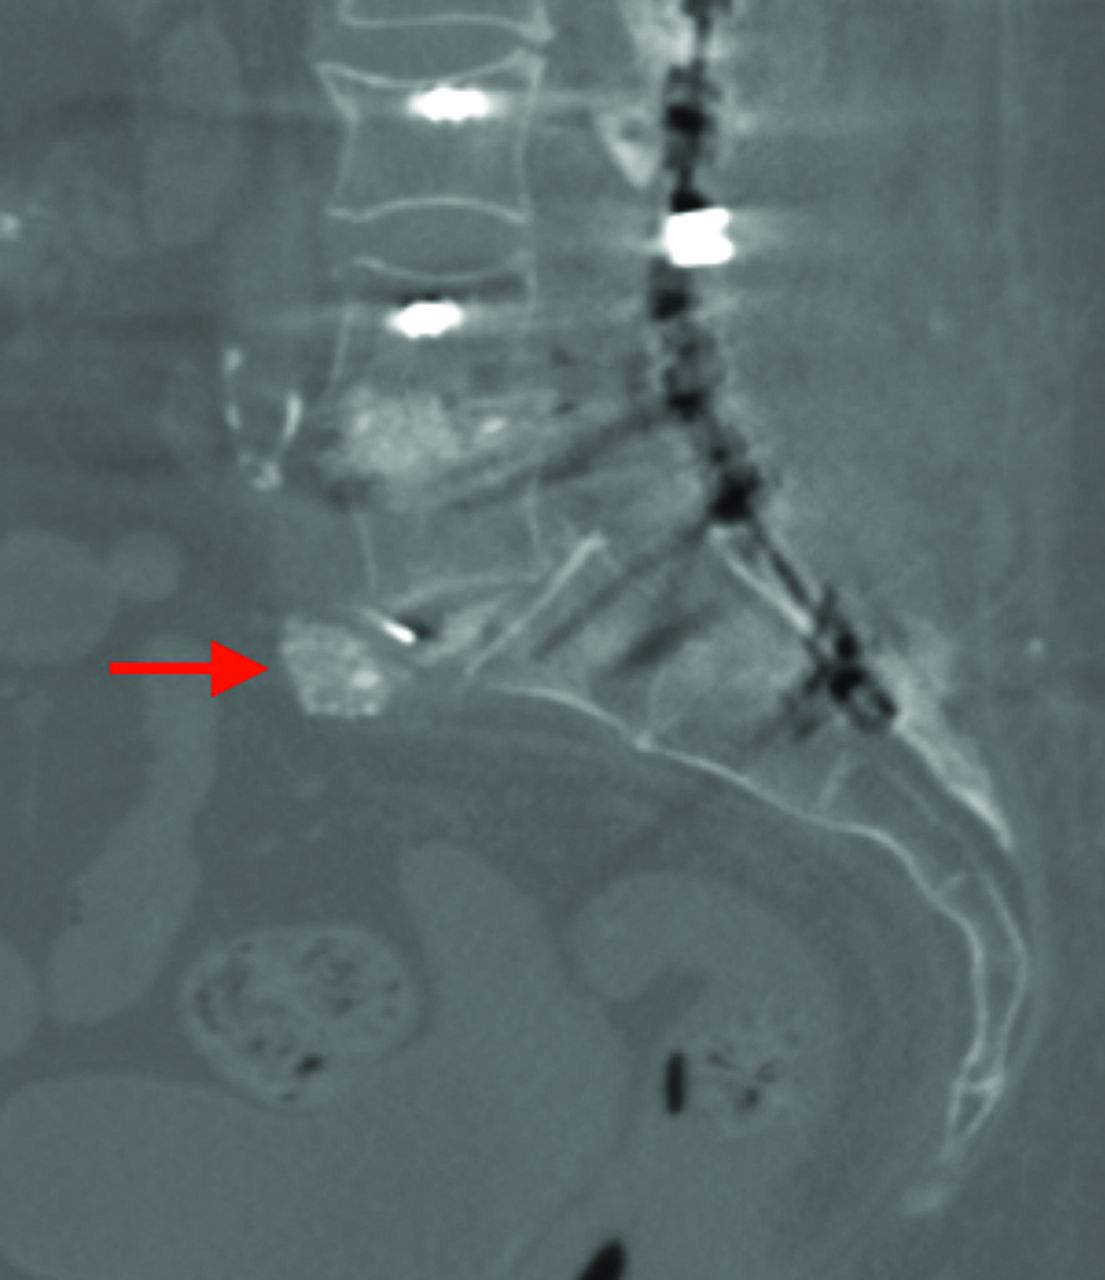

A, Schematic rendering of PSO. This is a posterior closing wedge osteotomy with resection of the posterior column, both pedicles, and part of the vertebral body. B, A 63-year-old man with prior postsurgical change of T12–L4 fusion instrumentation with very positive global sagittal imbalance (SVA = 9.7 cm). C, The same patient after L3 PSO and fusion instrumentation extension both cranially and caudally. The SVA is now within normal limits (2.0 cm). D, The same patient with a CT midsagittal bone window image demonstrating resection of the part of the L3 vertebral body extending to the superior endplate (arrow) with closure osteotomy at L3, consistent with pedicle subtraction osteotomy. This should not be mistaken for a posterior wedge compression fracture. E, A patient with a history of lumbar spinal fusion instrumentation, including complete intervertebral disc space fusion across L4–L5, underwent an L4 PSO and subsequently developed a fracture through the L4 vertebral body subjacent to the superior endplate, with resultant anterior subluxation of the superior fragment and L3 vertebral body relative to a dominant L4–L5 vertebral body fusion mass fragment.

On imaging, PSO may be mistaken for a posterior wedge compression fracture if one is not aware of this type of surgery. PSO is generally indicated for correction of SVAs of >10–12 cm, and it can provide 30°–40° of lordosis correction on average.31,32 In this technique, along with pedicle screw posterior fixation, wide laminectomies are performed at adjacent levels to protect the exiting nerve roots. Interbody fusion at levels above and below the osteotomy may be performed to avoid pseudoarthrosis.